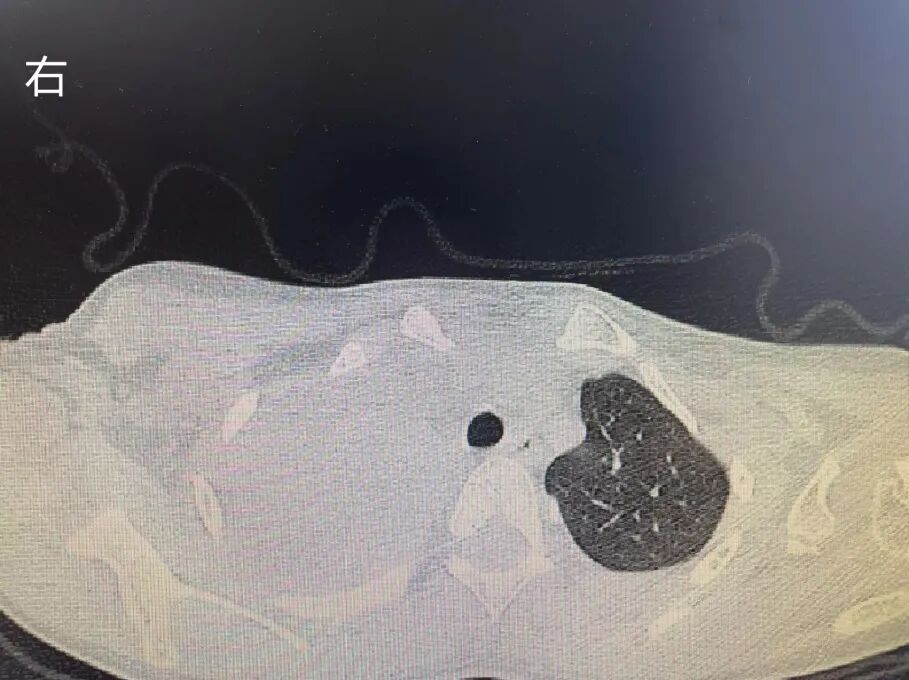

凜凜寒冬,冷風刺骨,流感、支原體暴發(fā)流行,各大醫(yī)院兒童發(fā)熱門診人滿為患,床位緊張。呼吸道疾病輕重難辨, “像云像霧又像風”。5歲的小蕊發(fā)熱5天,咳嗽劇烈,在外院就診后吃了幾天藥、打了1天抗生素針后沒有好轉,輾轉來到惠州市第三人民醫(yī)院兒科就診。胸片檢查顯示大片的“白色”,肺實變明顯。小蕊肺部感染嚴重,需要住院治療。入院完善相關檢查后,小蕊被確診為肺炎支原體感染,然而治療了2天癥狀都沒有改善,醫(yī)生建議完善胸部CT檢查。結果出來后,醫(yī)生倒吸了一口涼氣。“右側肺部大片炎癥伴有肺實變,右側胸腔有積液。”如果治療不及時,容易造成“閉塞性細支氣管炎、肺壞死”等嚴重并發(fā)癥。最后,小蕊被確診為“重癥肺炎支原體肺炎”。兒科鄧國雄副主任醫(yī)師向小蕊媽媽耐心地介紹了病情,建議進行電子纖維支氣管鏡探查。在征得家屬同意后,鄧國雄副主任醫(yī)師給小蕊做了電子支氣管鏡檢查并行肺泡灌。經(jīng)過治療,小蕊的癥狀得到了明顯改善,發(fā)熱和咳嗽均得到明顯好轉,復查胸片提示肺實變較前好轉吸收。如果孩子出現(xiàn)以下情況之一,需警惕重癥肺炎支原體感染:4.短時間抽血提示CRP、LDH、D-二聚體、ALT明顯升高;5.出現(xiàn)呼吸加快、血氧偏低,治療后癥狀沒有明顯改善或加重;6.既往有哮喘和原發(fā)性免疫缺陷病等疾病的癥狀加重;7.沒有及時使用阿奇霉素、紅霉素等大環(huán)內(nèi)酯類抗菌藥物。支氣管鏡是一項內(nèi)窺鏡檢查,一般從鼻腔插入,通過咽喉、會厭、聲門到氣管、支氣管、段支氣管、亞段支氣管及更細的支氣管。支氣管鏡檢查能將內(nèi)部情況真實地顯示在顯示屏幕上,呼吸道各個解剖部位的異常都能清晰看到。惠州三院兒科采取的電子支氣管鏡主要工作原理為,鏡前端的數(shù)碼攝像頭電荷耦合元件對觀察物攝像后,將信號通過電路傳入計算機圖像處理系統(tǒng),通過監(jiān)視器成像,其圖像清晰度大大優(yōu)于纖維支氣管鏡。4.喉部、氣管、支氣管肺發(fā)育不良和/或畸形;10.其他需要排除氣道及縱膈腫物、血管、淋巴管、食管發(fā)育異常、不明原因的長生發(fā)育異常、睡眠障礙者。嚴重心肺功能減退者、嚴重營養(yǎng)不良不能耐受手術者、嚴重心律紊亂、活動性大咯血者不宜做該項檢查。該檢查比較安全、并發(fā)癥較低,少數(shù)病例術后可能會出現(xiàn)一些常見的并發(fā)癥,如鼻粘膜出血、低血氧、低熱、術后陣發(fā)性咳嗽等,這些都是可逆的,一般在數(shù)小時左右可以緩解。